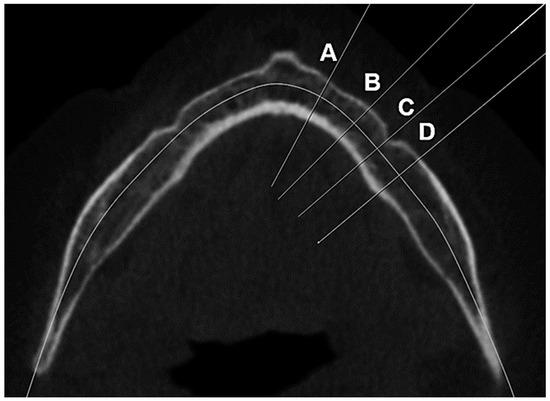

2.3.4. Determination of the Computed Tomography Cortical Index (CTCI) from Panoramic Reconstructed Image

2.3.3. Determination of the Computed Tomography Cortical Index (CTCI)

- C1: the outer edge of the cortical bone is flat and well demarcated;

- C2: the cortical bone layer is characterized by semilunar defects or one to two resorption lacunae;